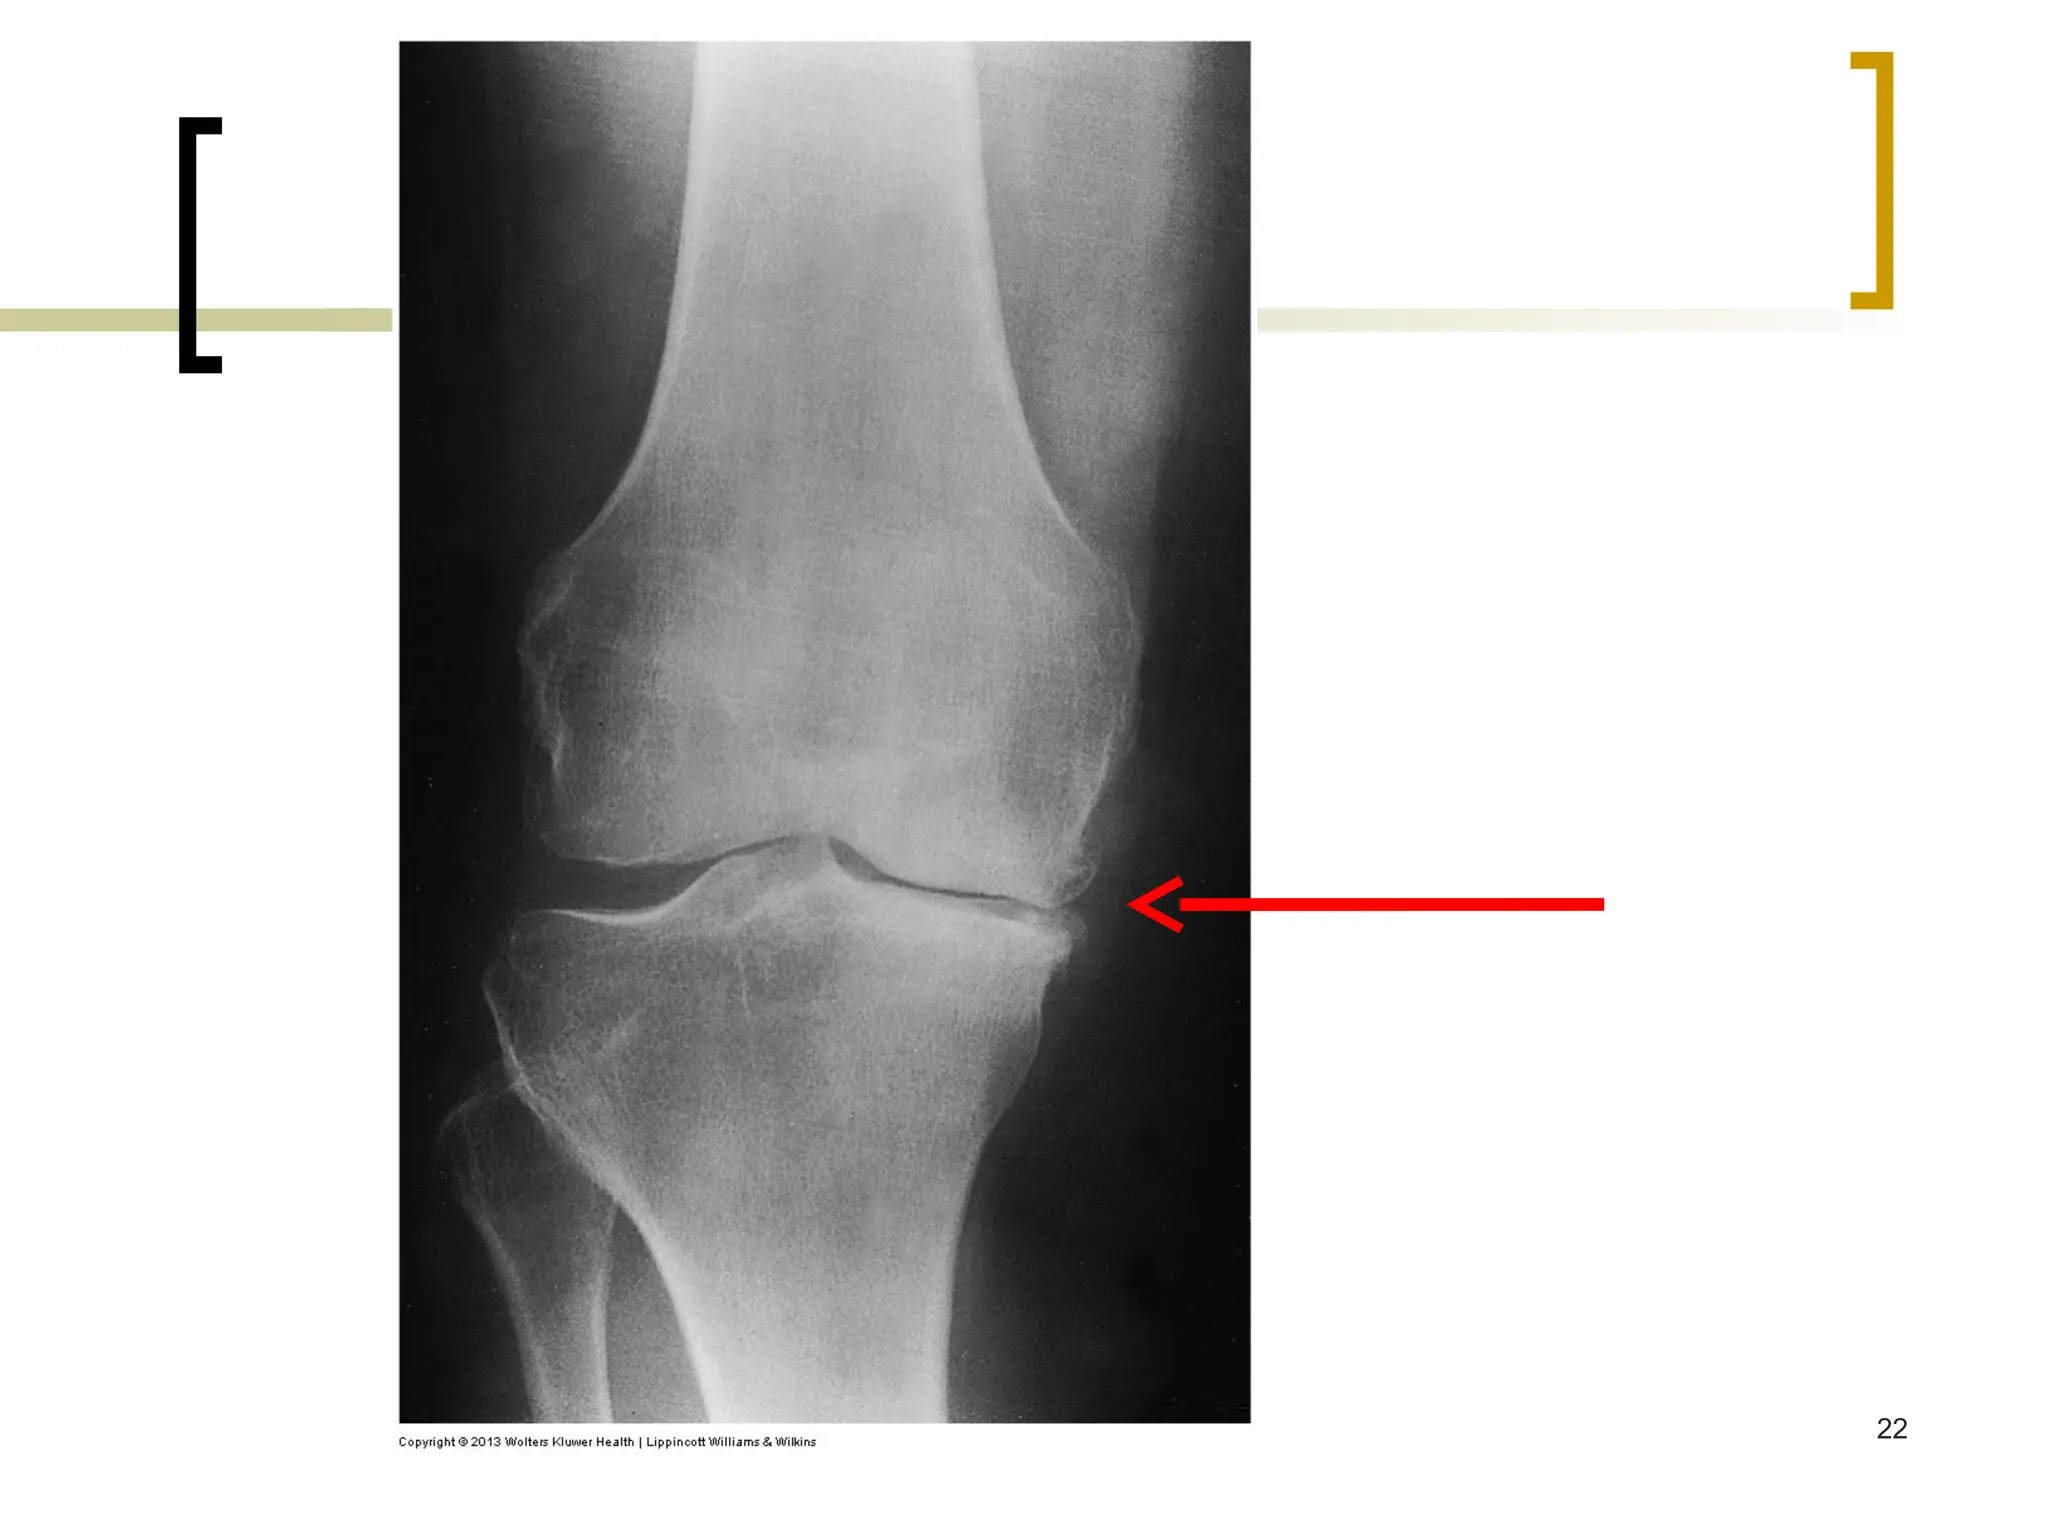

 Diagnostic Tests

 no specific laboratory tests useful in the dx

 Plain Radiographic Films:

 joint space narrowing, appearance of osteophytes in moderate

disease

 abnormal alignment of joints & joint effusion in late disease 20

b. Plain x-ray films of

the knee demonstrating

joint space narrowing

a. Physical findings of

joint enlargement &

genu varum (bandiness)

of the knees